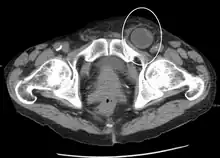

An incarcerated inguinal hernia as seen on CT

By far the most common hernias (up to 75% of all abdominal hernias) are inguinal hernias, which are further divided into the more common indirect inguinal hernia (2/3, depicted here), in which the inguinal canal is entered via a congenital weakness at its entrance (the internal inguinal ring), and the direct inguinal hernia type (1/3), where the hernia contents push through a weak spot in the back wall of the inguinal canal. An indirect inguinal hernia and a direct inguinal hernia can be distinguished by their positioning in relation to the inferior epigastric vessels. An indirect hernia is situated laterally to these vessels, whereas a direct hernia is positioned medially to them. Inguinal hernias are the most common type of hernia in both men and women. In some selected cases, they may require surgery.